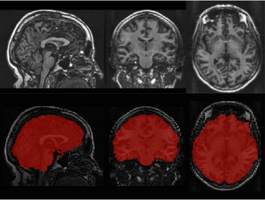

Skull stripping in a large and heterogeneous set of head MRI using

skull stripping

Application of 2D and 3D Deep Neural Network models to remove of the parts of 3D MR images that correspond to non-brain tissue.